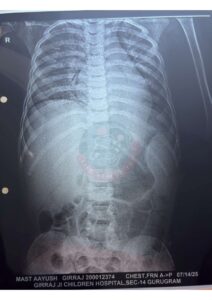

Patient: 5-day-old male child

Gestational Age at Birth: 28 weeks (Very Preterm)

Growth Status: AGA (Appropriate for Gestational Age)

Birth Weight: 1.1 kg (ELBW – Extremely Low Birth Weight)

Clinical Diagnosis:

Respiratory Distress Syndrome (RDS)

Apnea of Prematurity

Patent Ductus Arteriosus (PDA)

Current Condition:

The baby is critically ill, requiring NICU care, ventilatory/respiratory support, monitoring, and specialized neonatal management.